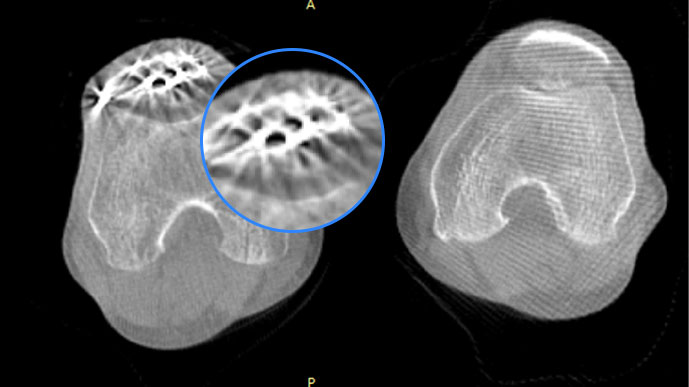

關閉金屬偽影校正

開啟金屬偽影校正